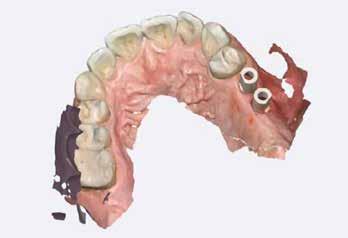

Digitális intraorális scan

Egy héttel a második műtét után intraorális szkennelést végeztünk Medit i500 scannerrel (Medit), a gyártó szkennelési protokollját követve (7. ábra). A gyógyulási csavarok eltávolítása után CERALOG scanbodykat (PEEK-titánötvözet csavar) helyeztünk el az implantátumokba. A fogszín meghatározását digitálisan, a Rayplicker (Borea) segítségével végeztük. A protetikai pótlás tervezéséhez poliphenilszulfon felépítményeket alkalmaztunk. Minden koronát digitálisan rendeltünk ugyanabból a fogászati laboratóriumból, és kerámiakoronákat választottunk minden esetben.

A koronák átadása

Átlagosan két héttel a szkennelés után a koronákat felhelyeztük, PEEK felépítményeket használtunk. Az összes koro-

na csavarozhatóan készült el. Mivel a négy páciens szigorúan a bioholisztikus megközelítés mellett döntött, a hat titán felépítménycsavart hat aranycsavarra (Holisticor csavarok) cseréltük ki. Ezeket az aranycsavarokat maximum 15 Ncm nyomatékkal húztuk meg. Titáncsavarok használata esetén legfeljebb 25 Ncm nyomatékot kell alkalmazni. A cég ajánlásának megfelelően az összes csavart legalább 5 perc elteltével újra meghúztuk a megfelelő nyomatékkal (15 Ncm). A csavarokat PTFE szalag védte, a fennmaradó csavarnyílásokat a cirkóniakoronával megegyező színű kompozitanyaggal fedtük. Az okklúziót ellenőriztük, és szükség esetén beállí-

tottuk (az okklúziós koncepciók alapján az implantációs pótlások nem voltak vezető fogak, és csak könnyű érintkezéseket alakítottunk ki, amelyeket artikulációs papírral ellenőriztünk). A páciensek instrukciókat kaptak a megfelelő szájhigiénére vonatkozóan, összpontosítva a fogköz kefékkel történő tisztítására. Végső kontroll röntgenfelvétel készült. A PEEK felépítmény nem radioopák, így az implantátum és a korona közötti távolság könnyen meghatározható a röntgenfelvételen: a felépítmény megfelelően illeszkedik az implantátumban, ha az implantátum válla és a korona alsó széle közötti rés 0,55 mm a röntgenfelvételen (8–11. ábra)